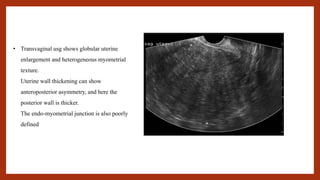

• Transvaginal usg shows globular uterine

enlargement and heterogeneous myometrial

texture.

Uterine wall thickening can show

anteroposterior asymmetry, and here the

posterior wall is thicker.

The endo-myometrial junction is also poorly

defined

• Transvaginal usgshows globular uterine enlargement and heterogeneous myometrial texture. Uterine wall thickening can show anteroposterior asymmetry, and here the posterior wall is thicker. The endo-myometrial junction is also poorly defined